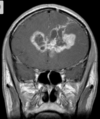

Aspecto de várias veias medulares dilatadas drenando para uma grande veia coletora, que por sua vez drena para o seio dural ou veia ependimária. Padrão em cabeça de medusa.